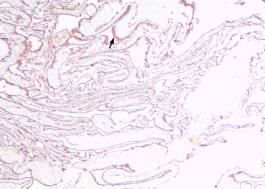

术后组织送病理检查,HE染色和免疫病理提示:考虑多囊性间皮瘤(图3),免疫病理:癌胚抗原M2A(D2-40)(+),抗平滑肌抗体(SMA)(-),血小板内皮细胞粘附分子(CD31)(-),高度糖基化I型跨膜糖蛋白(CD34)(-),Wilm肿瘤1(WT-1)(+),角蛋白(CK)(+),钙结合蛋白(+),细胞增殖相关核抗原(Ki-67)约1%(+)(图4)。

妇科蛋白膜怎么用这种妇科肿瘤无特异性,复发率高,有这些症状的姐妹小心_https://www.jmylbn.com_新闻资讯_第3张图3 肿瘤组织HE染色,放大10倍妇科蛋白膜怎么用这种妇科肿瘤无特异性,复发率高,有这些症状的姐妹小心_https://www.jmylbn.com_新闻资讯_第4张图4 肿瘤组织,免疫组化染色,

放大10倍,CK染色阳性